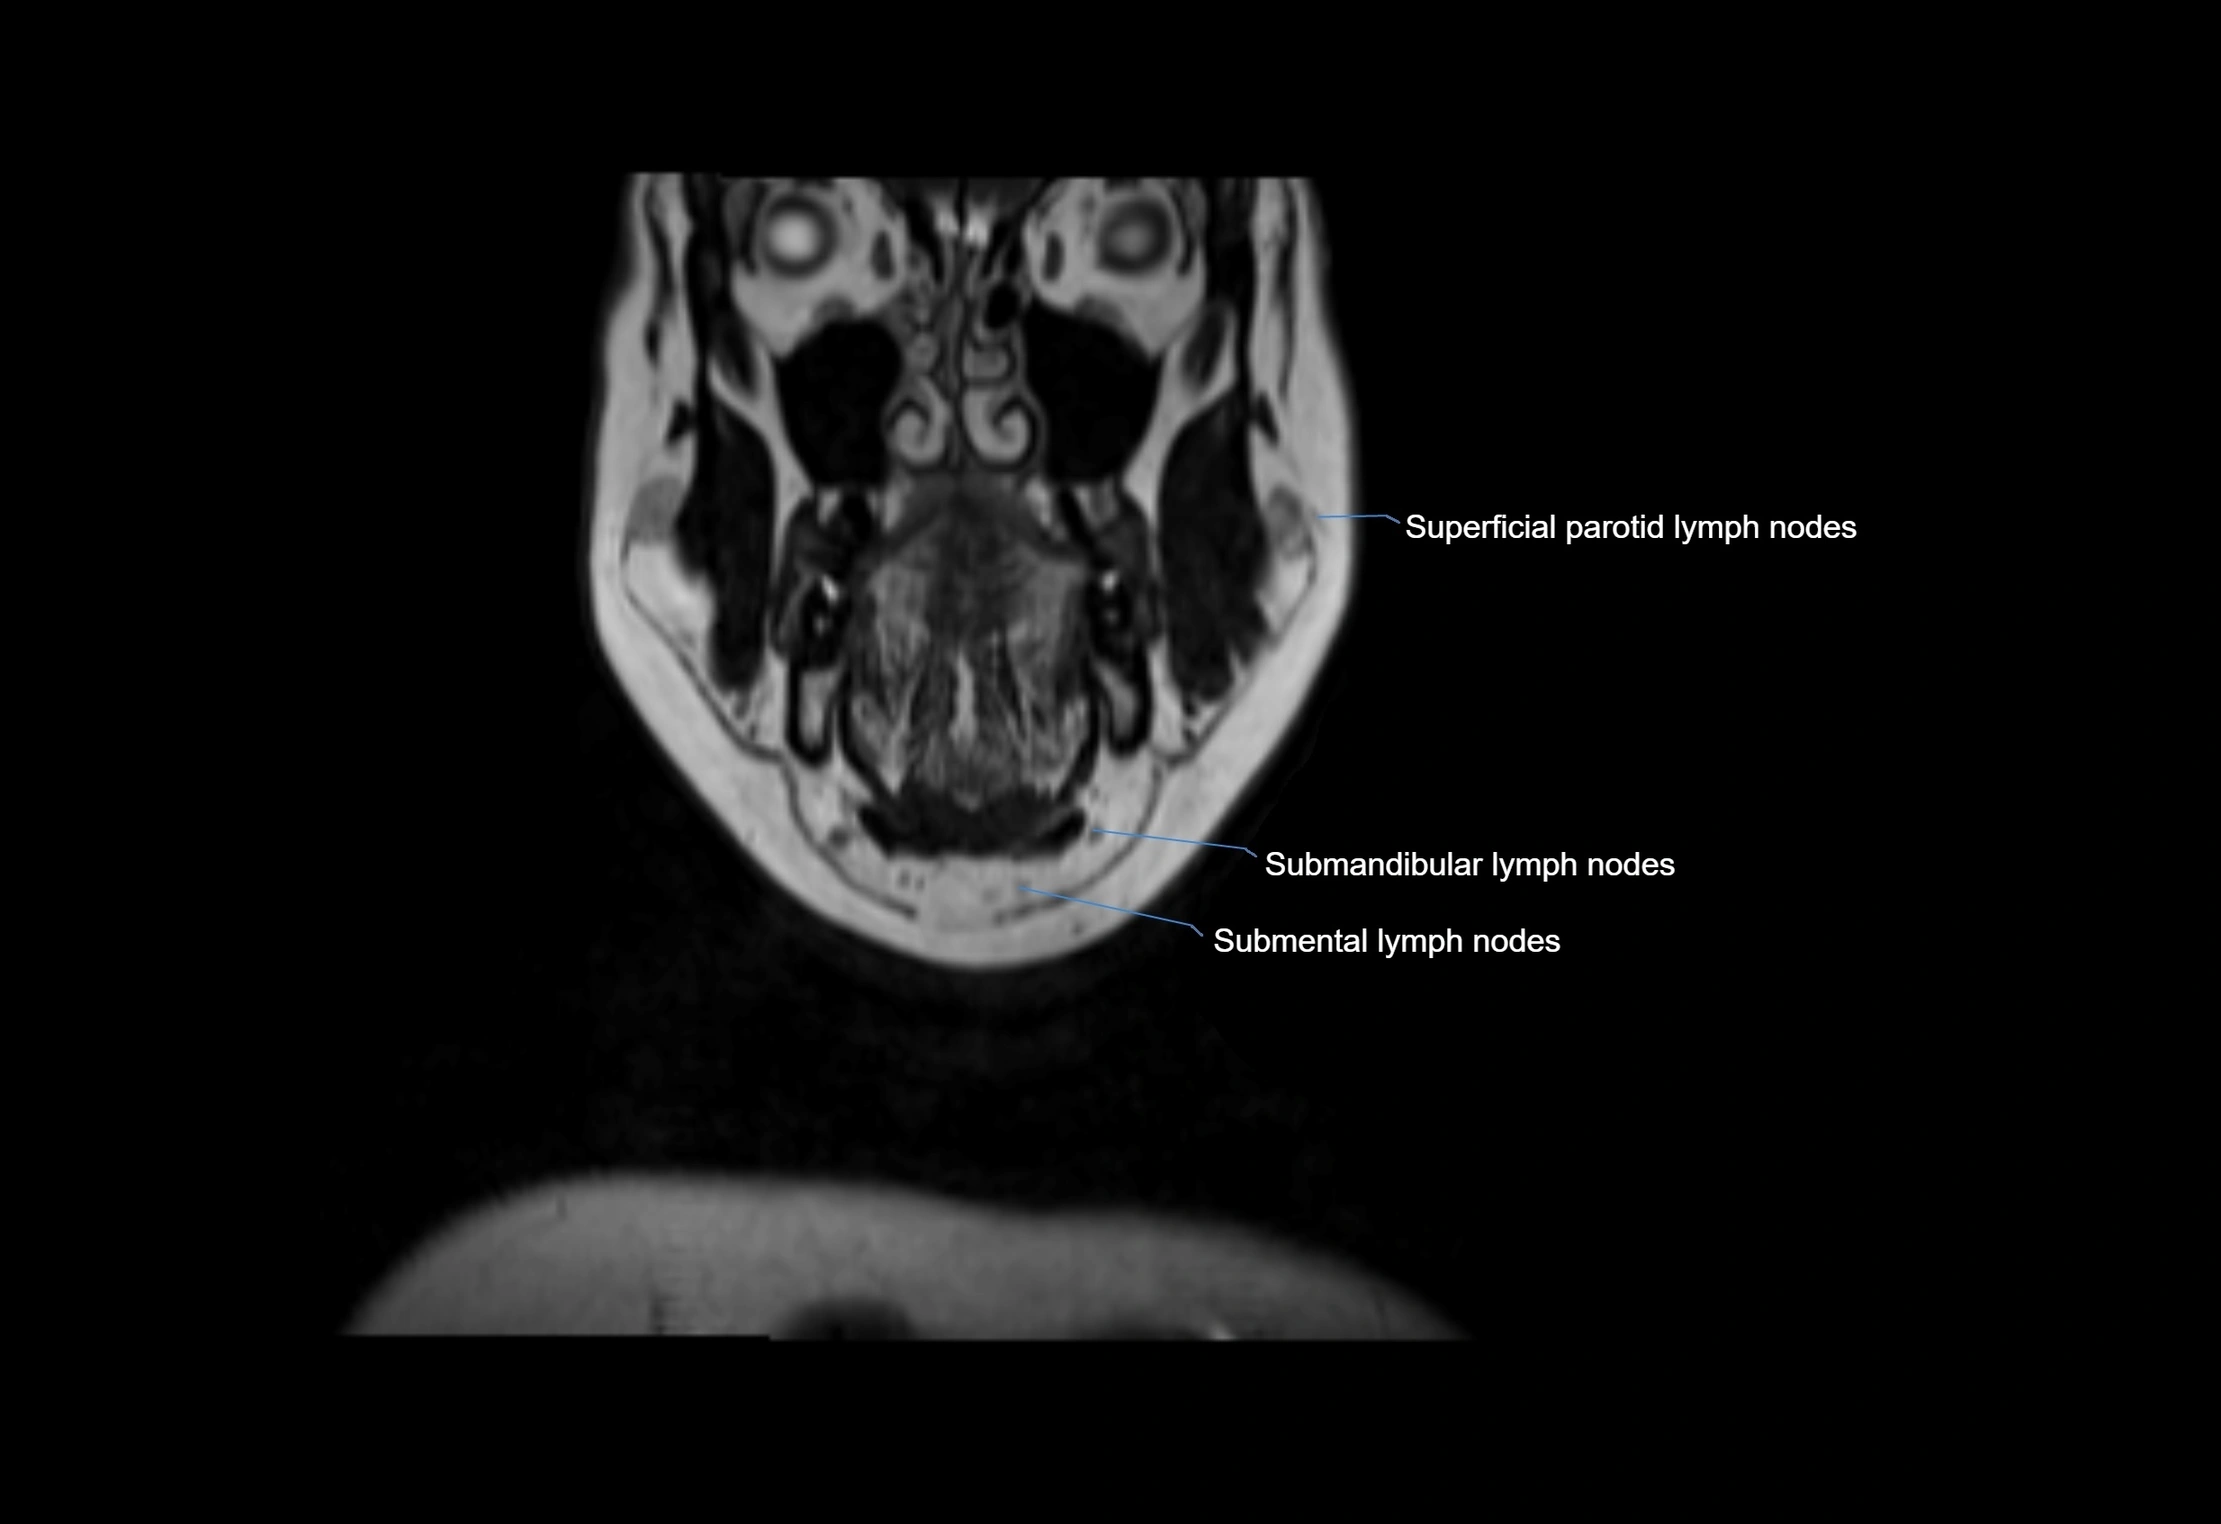

Location

• Found along primary lymph node chains, including preauricular, submandibular, parotid, and occipital regions

• Embedded in subcutaneous fat or superficial fascia, often lateral or posterior to primary nodes

MRI Appearance

T1-weighted images:

• Normal accessory nodes appear as small, oval hypointense to intermediate signal structures within subcutaneous fat

• Surrounded by hyperintense fat, enhancing contrast for visualization

• Pathological nodes may appear enlarged or rounded, sometimes with cortical thickening

MRI images

image